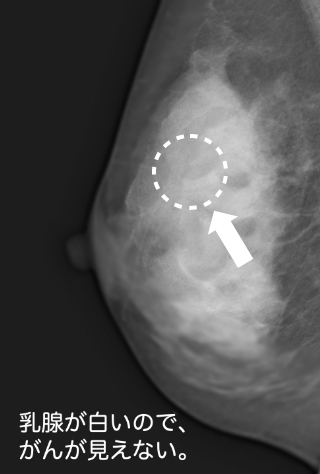

ところが、 50歳ぐらいまでの方の多くは、乳腺が豊富に存在し、これが マンモグラフィでのエックス線を通しにくい為、 乳房の中央部が白く(濃度が高く)写ります。これを 高濃度乳房といいます。

マンモグラフィの場合、 がんは白く写りますので「雪山の白ウサギ」をみつけるような感じになり、当然 がんがみつかりにくくなります。